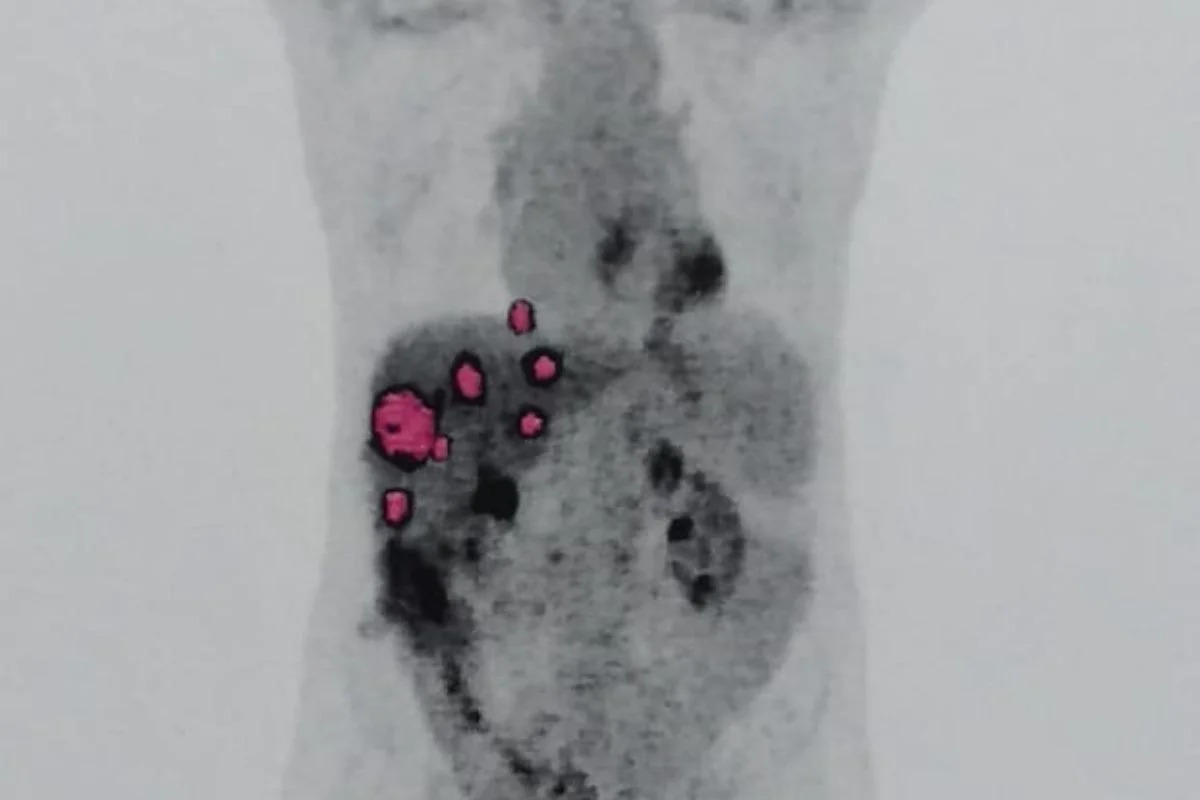

Um exame de DNA revelou que o paulista Geraldo Vaz Junior, de 58 anos, desenvolveu um câncer originado no fígado recebido em um transplante realizado em 8 de julho de 2023.

O adenocarcinoma foi descoberto em Junior sete meses depois, em março de 2024. No mesmo mês, o paciente foi submetido ao exame de DNA no Hospital Albert Einstein, onde foi realizado o transplante e também onde ele faz quimioterapia após a equipe médica identificar uma metástase do tumor no pulmão, em agosto do ano passado.

A genotipagem é clara e conclusiva. O resultado apontou que “as células da neoplasia não têm o mesmo genótipo das células do sangue periférico do paciente”, concluindo, então, que o tumor teve origem no órgão transplantado.

“Nesse contexto, a principal possibilidade é ser considerada que o adenocarcinoma da amostra AE24-021252 seja de origem doadora, e que tenha sido carreado juntamente com o transplante, provavelmente na forma de células isoladas ou micrometástases, manifestando-se clinicamente e radiologicamente, apenas durante o acompanhamento clínico”, afirma o exame.

“Cada pessoa tem uma ‘impressão digital genética’ única. Esse exame comparou o DNA das células do câncer com o DNA do Geraldo e com o DNA da pessoa doadora do fígado. O resultado foi conclusivo: as células do tumor têm o DNA do doador, não do paciente”, explicou a médica.

O laudo hospitalar ainda evidencia que as células cancerosas do fígado possuem cromossomos sexuais femininos (XX), enquanto Geraldo, sendo homem cis, possui cromossomos masculinos (XY). “É como se as células do tumor ‘assinassem’ que vieram de uma mulher, não dele”, comentou a especialista.

Para o oncologista, é certo que a doadora teve câncer em algum momento da vida. “Se foi feito o teste e qualificou que veio do doador, não tem jeito, esse câncer veio junto com o fígado. Não é um câncer novo, o doador com certeza teve um câncer em algum momento, e ao ser feita a remoção do órgão, ele tinha células cancerosas presentes”, explicou.